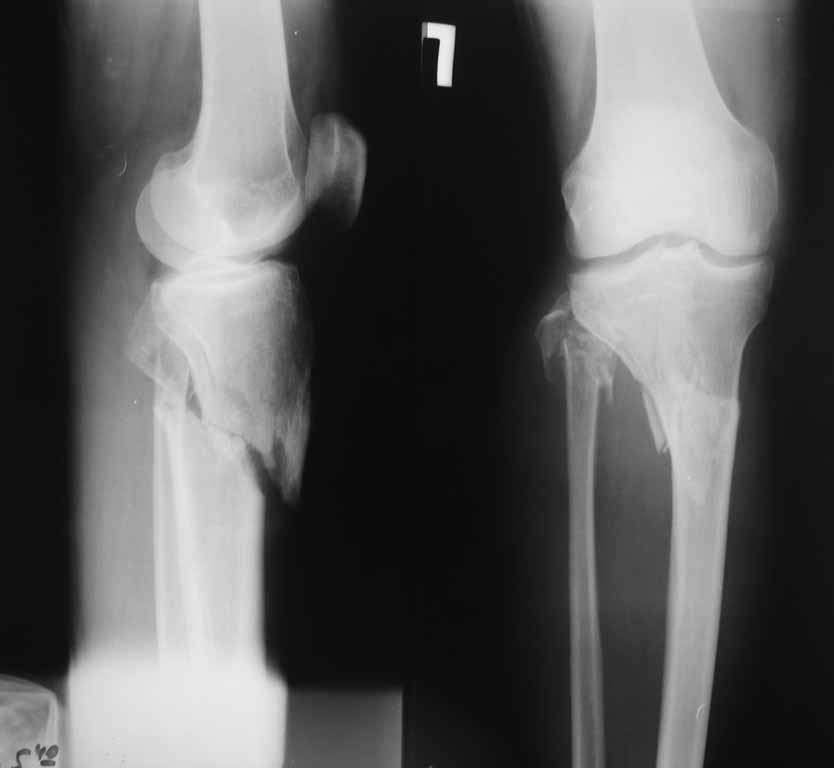

Мужчина 40 лет получил закрытый внутрисуставной перелом верхней трети костей правой голени в результате ДТП (см. рентгенограммы). Какой фиксатор подошел бы для данного перелома понятно, однако у пациента имеется по передне-наружной поверхности верхней трети голени ссадина и участок некроза кожных покровов (см. фото), поэтому латеральная мыщелковая пластина не подойдет, а медиальных пластин у фирм-производителей нет. Пациент может приобрести современный имплант, но какой….???? Слышал, что некоторые ставят, например, левую латеральную мыщелковую пластину по медиальной поверхности правой голени – работает ли это? Каким фиксатором и каких фирм прооперировали бы Вы??? Заранее СПАСИБО!!!